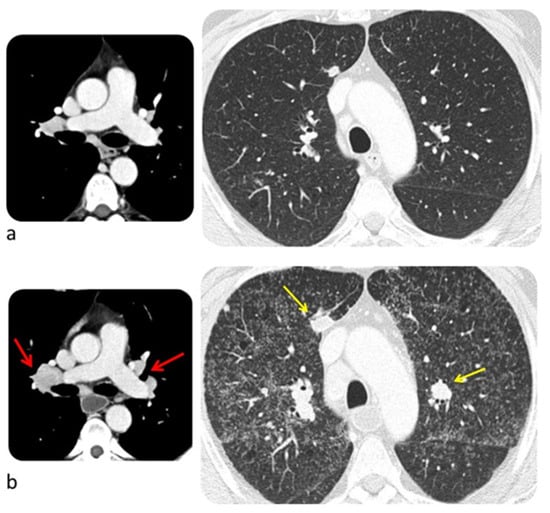

6.3. Lung